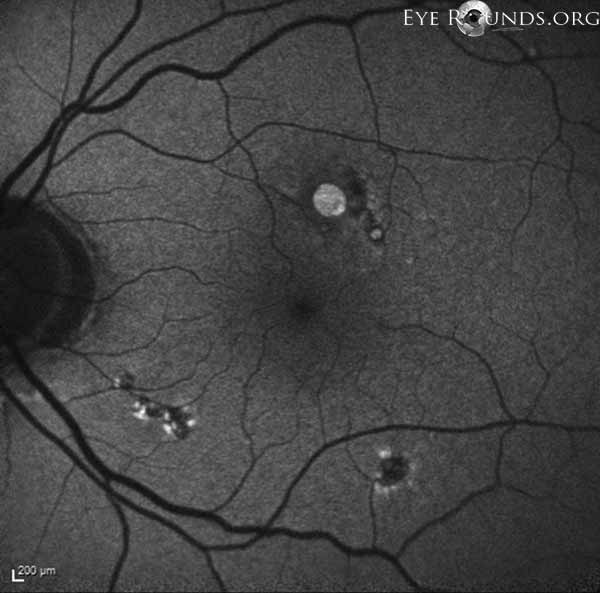

Fig 9: Autofluorescence imaging: hypo and hyper-autofluorescence in areas of pigmentary changes, possibly in areas of forceps grasping during ILM peeling. There is increased-autofluorescence in the area of the eccentric full-thickness macular hole.